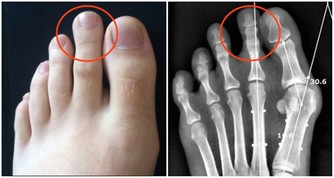

因為有了這一次治療頸椎和胸椎的經驗以後,發現很多患有頸椎病、腰椎病的人,在頸椎以下、腰椎以上相連接的椎體上,均存在著錯位,因此,得出一條重要結論:頸椎有病連著肺,腰椎有病連著胃。

這句話講的是什麼意思呢?頸七椎向下相連的是胸椎的一椎、二椎,這兩個椎體與肺相通,是通往肺的通路,當頸椎扭傷一定牽連到胸椎的一、二椎;腰椎向上相連的是胸十椎、十一椎、十二椎,十一椎、十二椎與脾、胃相通,是通往脾胃的通路,當腰椎扭傷一定牽連到胸十、十一椎。

如此看來,我們在對頸椎錯位治療的同時,要顧及到胸椎的一、二椎的檢查和治療,腰椎錯位的治療,要顧及到胸椎的十、十一、十二椎的檢查和治療,與頸、腰椎相連接錯位椎體的治療,即是對本病的恢復起到治療作用,同時,也有利於頸、腰椎的治療。這些與之相連的椎體錯位,患者也一定會出現相聯繫臟腑的病症反應。以上對頸、腰椎檢查方法,對病症的判斷,以及治療的範圍,做為醫者不可不知也。

頸椎下端和腰椎上端的這些部位,往往是在臨床中被遺忘的角落,所以,既影響頸、腰椎的治療,也影響與之相連病症的治療效果。醫者在治療頸椎腰椎的同時,一定要檢查鄰近胸椎椎體的排列狀態,頸椎的治療要注意到肺(胸一、二椎),腰椎的治療要注意到胃(胸十、十一椎),這是治療頸椎腰椎病症的關鍵。